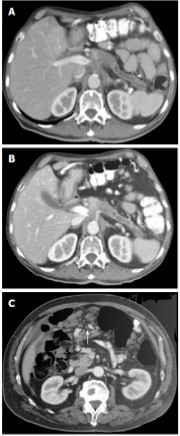

• Görüntüleme: USG, BT, MR/MRCP, endoskopik ultrason (EUS)

• Endoskopik yöntemler: ERCP (tedavi edici/ tanısal amaçlı kullanılabilir)